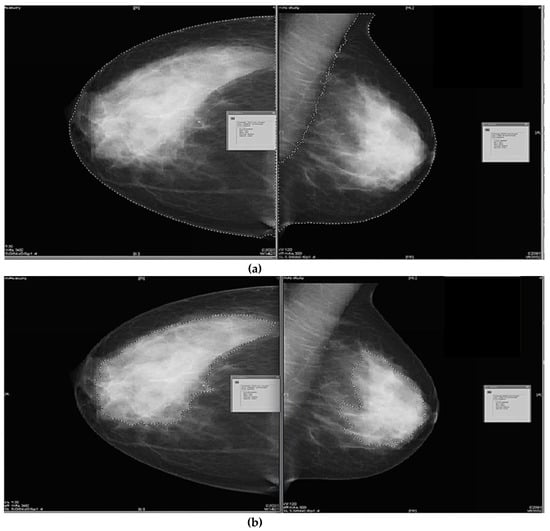

2.3.1. Semi-Subjective Density Assessment

2.3.2. Semi-Objective Density Assessment